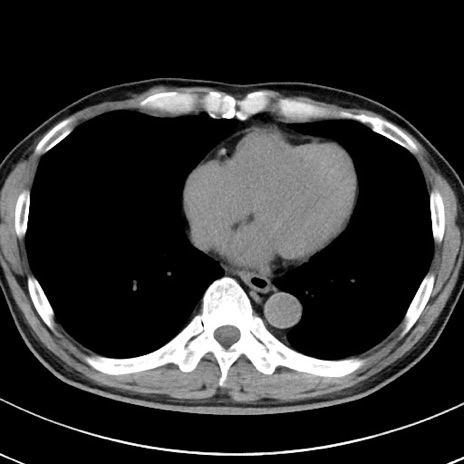

【腹部TIPS】症例29 参考症例 CT(横断像)

症例

70歳代男性